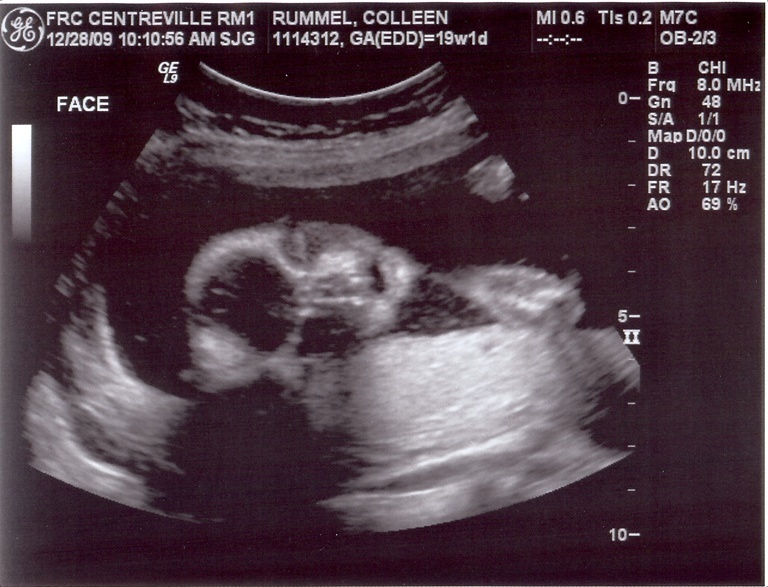

Yep, that sure is a boy! 🙂 Since you didn’t lead me astray in the daycare referral – who is your OB? Do you like him/her? I see you have Centreville on your sonogram. I had Tay in Virginia Hospital Center (Arlington) when we lived there, and my OBs are all right next door to there. Convenient for when I’m at work (I also work next door) but not so convenient for things like having babies and such. Would like to find someone down here…

So cute. And if you have to ask what he’s doing back there, you probably don’t want to know.